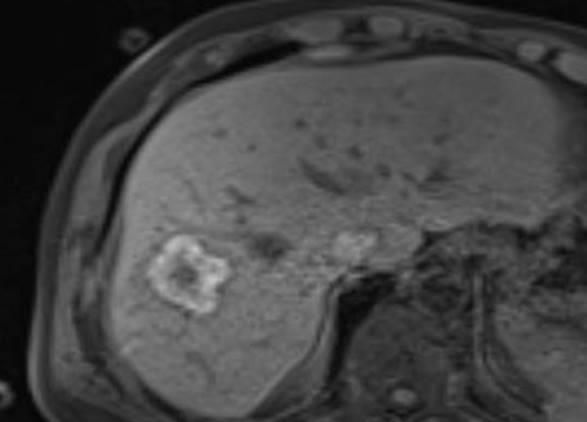

Eine Voraussetzung für die vollständige chirurgische Entfernung von Knochen- und Weichteiltumoren ist die präzise Erkennung der Tumorausdehnung und der Tumorgrenzen. Mit der Kernspintomographie (MRT) kann das Tumorgewebe exzellent von gesundem Gewebe abgegrenzt werden und somit die Ausdehnung vor der Operation bestimmt werden. Nach der kernspintomographischen Bestimmung der Tumorausdehnung werden unter kontinuierlicher MRT-Bildgebung die Grenzen des Tumors markiert. Die Marker werden mit einer Nadel ins angrenzende gesunde Gewebe eingebracht. Die Markierung kann am Tage vor der Operation durchgeführt werden. Alternativ ist die Tumormarkierung auch mit anderen bildgebenden Verfahren möglich, z.B. mit der Computertomographie oder dem Ultraschall.

Abbildung: Bei diesem Patienten wurde ein im Röntgen nur schlecht sichtbarer Knochentumor vor der Operation unter MRT-Kontrolle mit kleinen röntgendichten Spiralen („Coils“) markiert. Damit hat der Operateur eine optimale Darstellung des Tumorbereichs bzw. der Tumorgrenzen und kann gezielter, schonender und effektiver operieren.